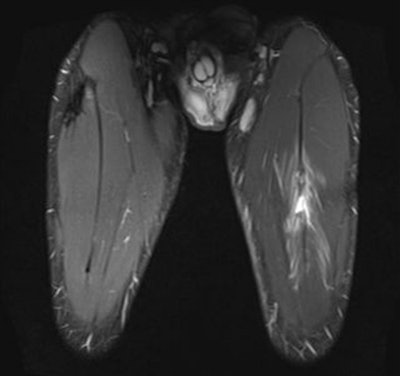

the musculotendinous junction. Note the feathery edema pattern within the muscle radiating from the primary injury site. Below: Extended field-of-view ultrasound demonstrates loculated hematoma at the musculotendinous junction with surrounding increased reflectivity within the rectus femoris muscle. All images courtesy of Dr. Justin Lee, Chelsea and Westminster Hospital.

MRI was performed on different systems at 1.5 or 3 tesla. In most instances, skin markers (cod liver oil capsule) were placed at the site of maximum symptoms. Sequences were dependent on the original institution at which the examination was undertaken, and a typical protocol included a combination of axial, coronal, and sagittal short tau inversion recovery (STIR)/T2-weighted fat-suppressed/proton density-weighted fat-suppressed sequences followed by axial and sagittal T1-weighted sequences. For the study, the images were electronically transferred to a secure electronic database and reviewed using the 32-bit OsiriX DICOM viewer system on the Apple platform.

Two specialist musculoskeletal radiologists independently reviewed all MRI studies and graded the injuries according to the new classification system. All images were reviewed by both radiologists initially (round 1) and again after a four-month period (round 2). When more than one muscle was involved, the muscle with the worst injury was scored. An independent observer, not involved in the study, performed all the statistical analyses.